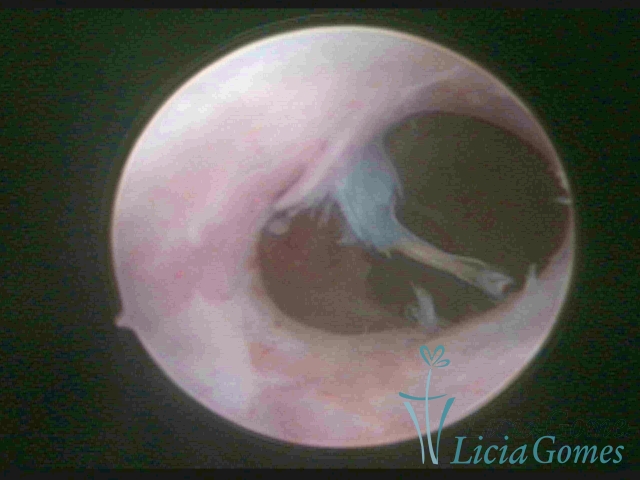

SINÉQUIA TIPO MUCOSA

As Sinéquia uterinas são cicatrizes (aderências) entre as superfícies das paredes uterinas, que podem ocorrer após manipulação cirúrgica, ou curetagem uterina, ou após um processo inflamatório na cavidade uterina (endometrite), podendo levar a alterações menstruais, infertilidade, e complicações obstétricas, como abortamento, parto prematuro.